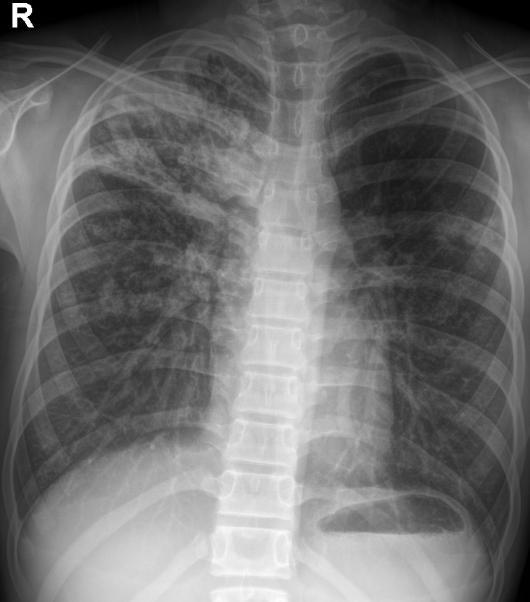

我的好友丹丹,老家有一个表妹,今年16岁,1年前无明显诱因出现右臀部酸痛,伴畏寒、发热、午后低热、盗汗,无双下肢放射痛,并出现左臀部皮肤红肿、破溃、流脓,曾在当地卫生院间断诊治,予以口服药物治疗,效果差,后逐渐出现右臀部外侧皮肤破溃、流脓,经自行口服药物后窦道自行愈合后,周围再次出现流脓,经久不愈,时有脓液流出。丹丹前两天回到老家,把表妹接到我院住院治疗。骨科专科检查发现右臀部一个约0.5x0 5 cm大小窦道口,按压周围可见黄色干酪样分泌物流出,局部可见肉芽组织,无红肿,周围可见多个窦道口疤痕。胸部X线检查:右上.中肺野及左中肺野可见片状.斑片(点)状.条索状阴影,边缘清晰,密度均匀。骨盆CT检查:右侧骶髂关节面骨质破坏、硬化,正常关节结构破坏,臀部软组织内可见囊性密度不均之肿块,影像诊断:右上.中肺.左中肺结核,右侧骶髂关节结核伴髂内肌冷脓肿形成、关节半脱位。

骶髂关节结核常见影像学表现为骨质破坏,死骨形成,关节间隙增宽或变窄,周围脓肿形成,部分伴有窦道。骨盆的X线平片检查可明显的看出骨质的改变,部分脓肿,但由于解剖结构的特殊性,无法显示全部的关节间隙。CT的密度分辨率较高,能够清晰的显示骨破坏程度、部位以及范围,对死骨、脓肿的形成及部位、窦道、囊肿等能够直观的检查,可以发现到X线检查难以观测的生理性骨化和病理性改变。

骶髂关节结核影像学表现:滑膜型结核早期关节囊肿胀,关节间隙增宽,继而侵及关节软骨和关节面;骨型结核早期在骶髂关节的骶骨或髂骨端见到孤立的圆形或椭圆形破坏区,边缘清楚,继而病变累及关节软骨和滑膜,导致关节边缘模糊、毛糙,骶髂关节前下部受累最早,且以髂骨侧破坏最严重。随着病变的进展,滑膜被增生的肉芽组织替代,干酪样坏死物聚集、侵蚀,死骨形成,最终使全关节受累,韧带软化、松弛,关节间隙增宽,这有别于其他大关节。由于骶髂关节结核的骨质疏松常不如其他关节明显,而往往显示有骨质增生硬化征象。关节破坏严重者,可造成病理性半脱位。大多有冷脓肿形成,多发生在臀部,有时在腹股沟、髂窝区,当脓肿增大,张力增高时,常自行破溃并沿着薄弱的组织间隙蔓延形成窦道。